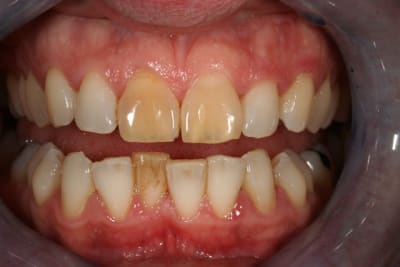

Un cas de blanchiment interne .

Cas simple et pourtant ... j'ai été obligé de prendre un risque . Lequel ?

PS/ Je prolonge le ttt jusqu'à la semaine prochaine en espérant gagner encore un poil sur l'opacité .

C'est un blanchiment unitaire sur dent vivante ayant eu traumatisme.

C'est un blanchiment interne comme si l'endo était faite (après recherche effrénée d'un hypothétique canal), et après contrôle +++ d'une isolation +++ . La patiente n'a aucun souvenir d'un traumatisme sur cette dent .

Le protocole est le même que pour une dent dépulpée ; isolation en regard présumé du canal , un peu plus parce que j'ai cherché un moment en plusieurs séances . Perborate , et voilà .

3 séances à 7 jours d'intervalles .

Si on décide d'être le moins invasif , j'ai jugé raisonnable de tenter quand même malgré l'impossibilité de repérage de l'entrée du canal . Faire une facette c'est passer un cap , et je n'ai de prothésiste capable de reproduire les stries visibles sur la photo de départ de tout façon donc je n'ai compté que sur moi même .